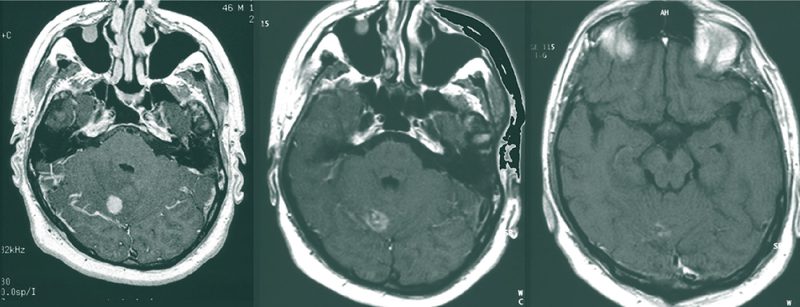

Strahlentherapie von Hirnmetastasen

Die Inzidenz von Hirnmetastasen nimmt proportional zur verlängerten Überlebenszeit zu, wodurch die Prognose deutlich verschlechtert wird. Intensitätsmodulierte Techniken der Strahlentherapie können den Hippocampus schonen.... Dieser Inhalt ist nur für Benutzer…